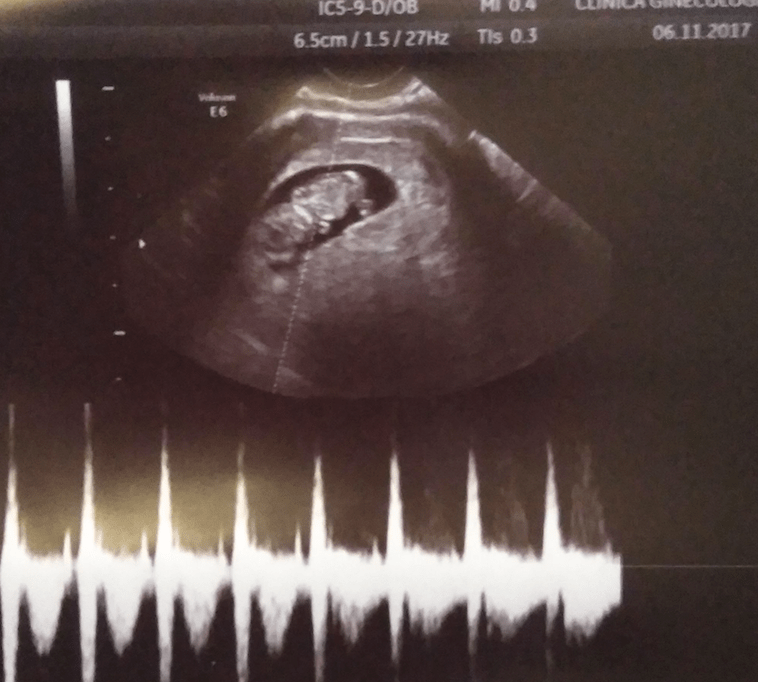

Titi está perfecto, crece a toda máquina. Su medida corresponde a 9 semanas y 4 días, su corazón late como una locomotora y nos saluda con su mano/pala. Una de las cosas que más nos impactó a los dos fue verlo moverse. ¡¡porque se mueve!!… ¡¡¡y es una movida!!!

Del susto, el futuro padre, se golpeó la cabeza con un dispensador de papel anclado en la pared. Acto seguido balbuceos y risas. Como yo me reí, Titi también se movió.

Gorka dijo: ¡¡hace cosas!!, yo respondí: ¡¡claro, es que es muy listo!!…